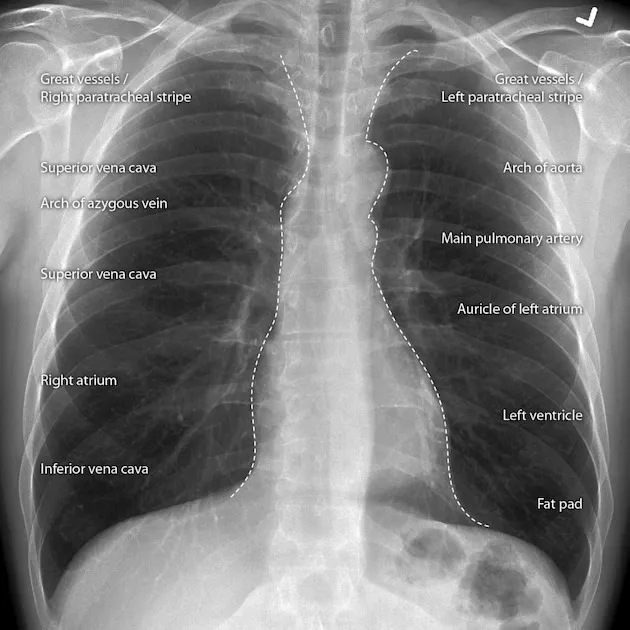

PA View Borders: The heart's edges are formed by specific chambers and great vessels.

- Right: Superior Vena Cava (SVC) and the Right Atrium (RA).

- Left: Aortic knob, main Pulmonary Artery, Left Atrial appendage, and the Left Ventricle (LV).

The cardiac silhouette on a PA chest X-ray presents distinct borders formed by different chambers and great vessels.

- Right Heart Border: Primarily formed by two convexities.

- Superior: Superior Vena Cava (SVC)

- Inferior: Right Atrium (RA)

- Left Heart Border: Composed of four "bumps" or convexities.

- Aortic Knob: The arch of the aorta.

- Main Pulmonary Artery (MPA): The "pulmonary bay".

- Left Atrial Appendage (LAA): Not always visible; enlargement suggests mitral stenosis.

- Left Ventricle (LV): Forms the cardiac apex.

- 📌 Mnemonic (Superior to Inferior): All People Love Lunges

⭐ Cardiothoracic Ratio (CTR): On a PA chest X-ray, the transverse cardiac diameter should be less than 50% of the transverse thoracic diameter. A CTR > 0.5 is a key indicator of cardiomegaly.

⭐ Cardiothoracic Ratio: On a PA film, the maximum horizontal cardiac diameter should be less than 50% of the maximum horizontal thoracic diameter. A ratio >0.5 is a key indicator of cardiomegaly.